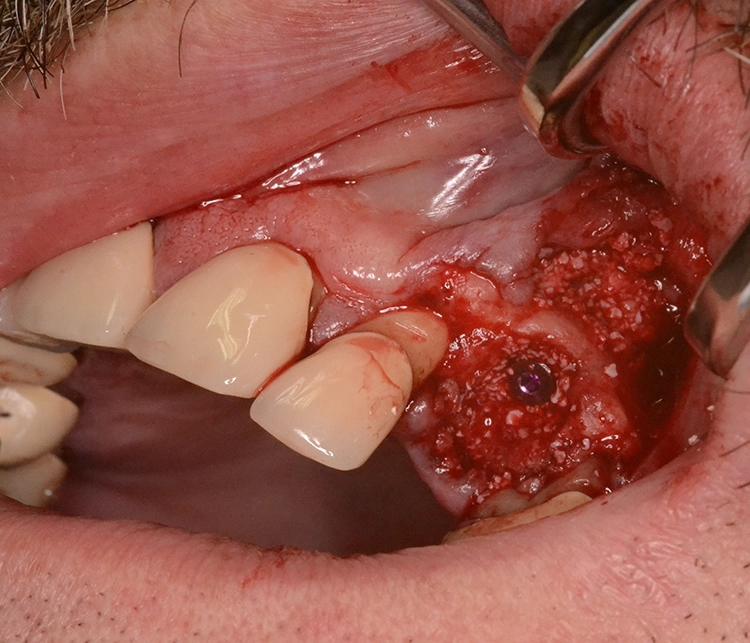

Im präoperativ angefertigten DVT (Abb. 3b und c) zeigte sich um die Wurzelspitze ein chronisches Entzündungsgeschehen, welches die vestibuläre Lamelle im apikalen Wurzelbereich des Zahnes 23 komplett aufgelöst hat. Da jedoch der Bereich direkt apikal von 23 nicht vom Geschehen betroffen war, fiel die Entscheidung zur Sofortimplantation auch, da der Patient blutverdünnende Medikamente einnehmen musste, welche durch Kombination von Extraktion und Implantation nur einmal abgesetzt werden mussten. In diesem Fall war aufgrund des Knochendefektes die Bildung eines Volllappens mit Entlastung unumgänglich.

Anschließend wurde der Knochendefekt mit kortikospongiösem Knochengranulat aufgefüllt und mit einer langsam resorbierenden Kollagenmembran versorgt (Abb. 3e und f). Das OP-Gebiet musste im Anschluss aufgrund der Augmentation vollständig gedeckt werden (Abb. 3g).